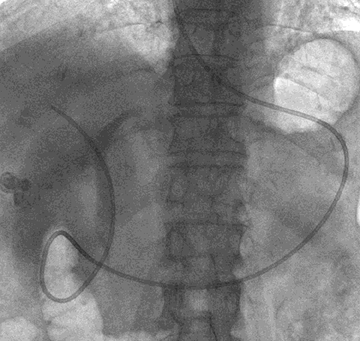

Endoscopic submucosal dissection for early gastric cancer using a cross-counter technique

Okamoto K, Okamura S, Muguruma N, Kitamura S, Kimura T, Imoto Y, Miyamoto H, Okahisa T, Takayama T

Surg Endosc, 2012;26:3676-3681